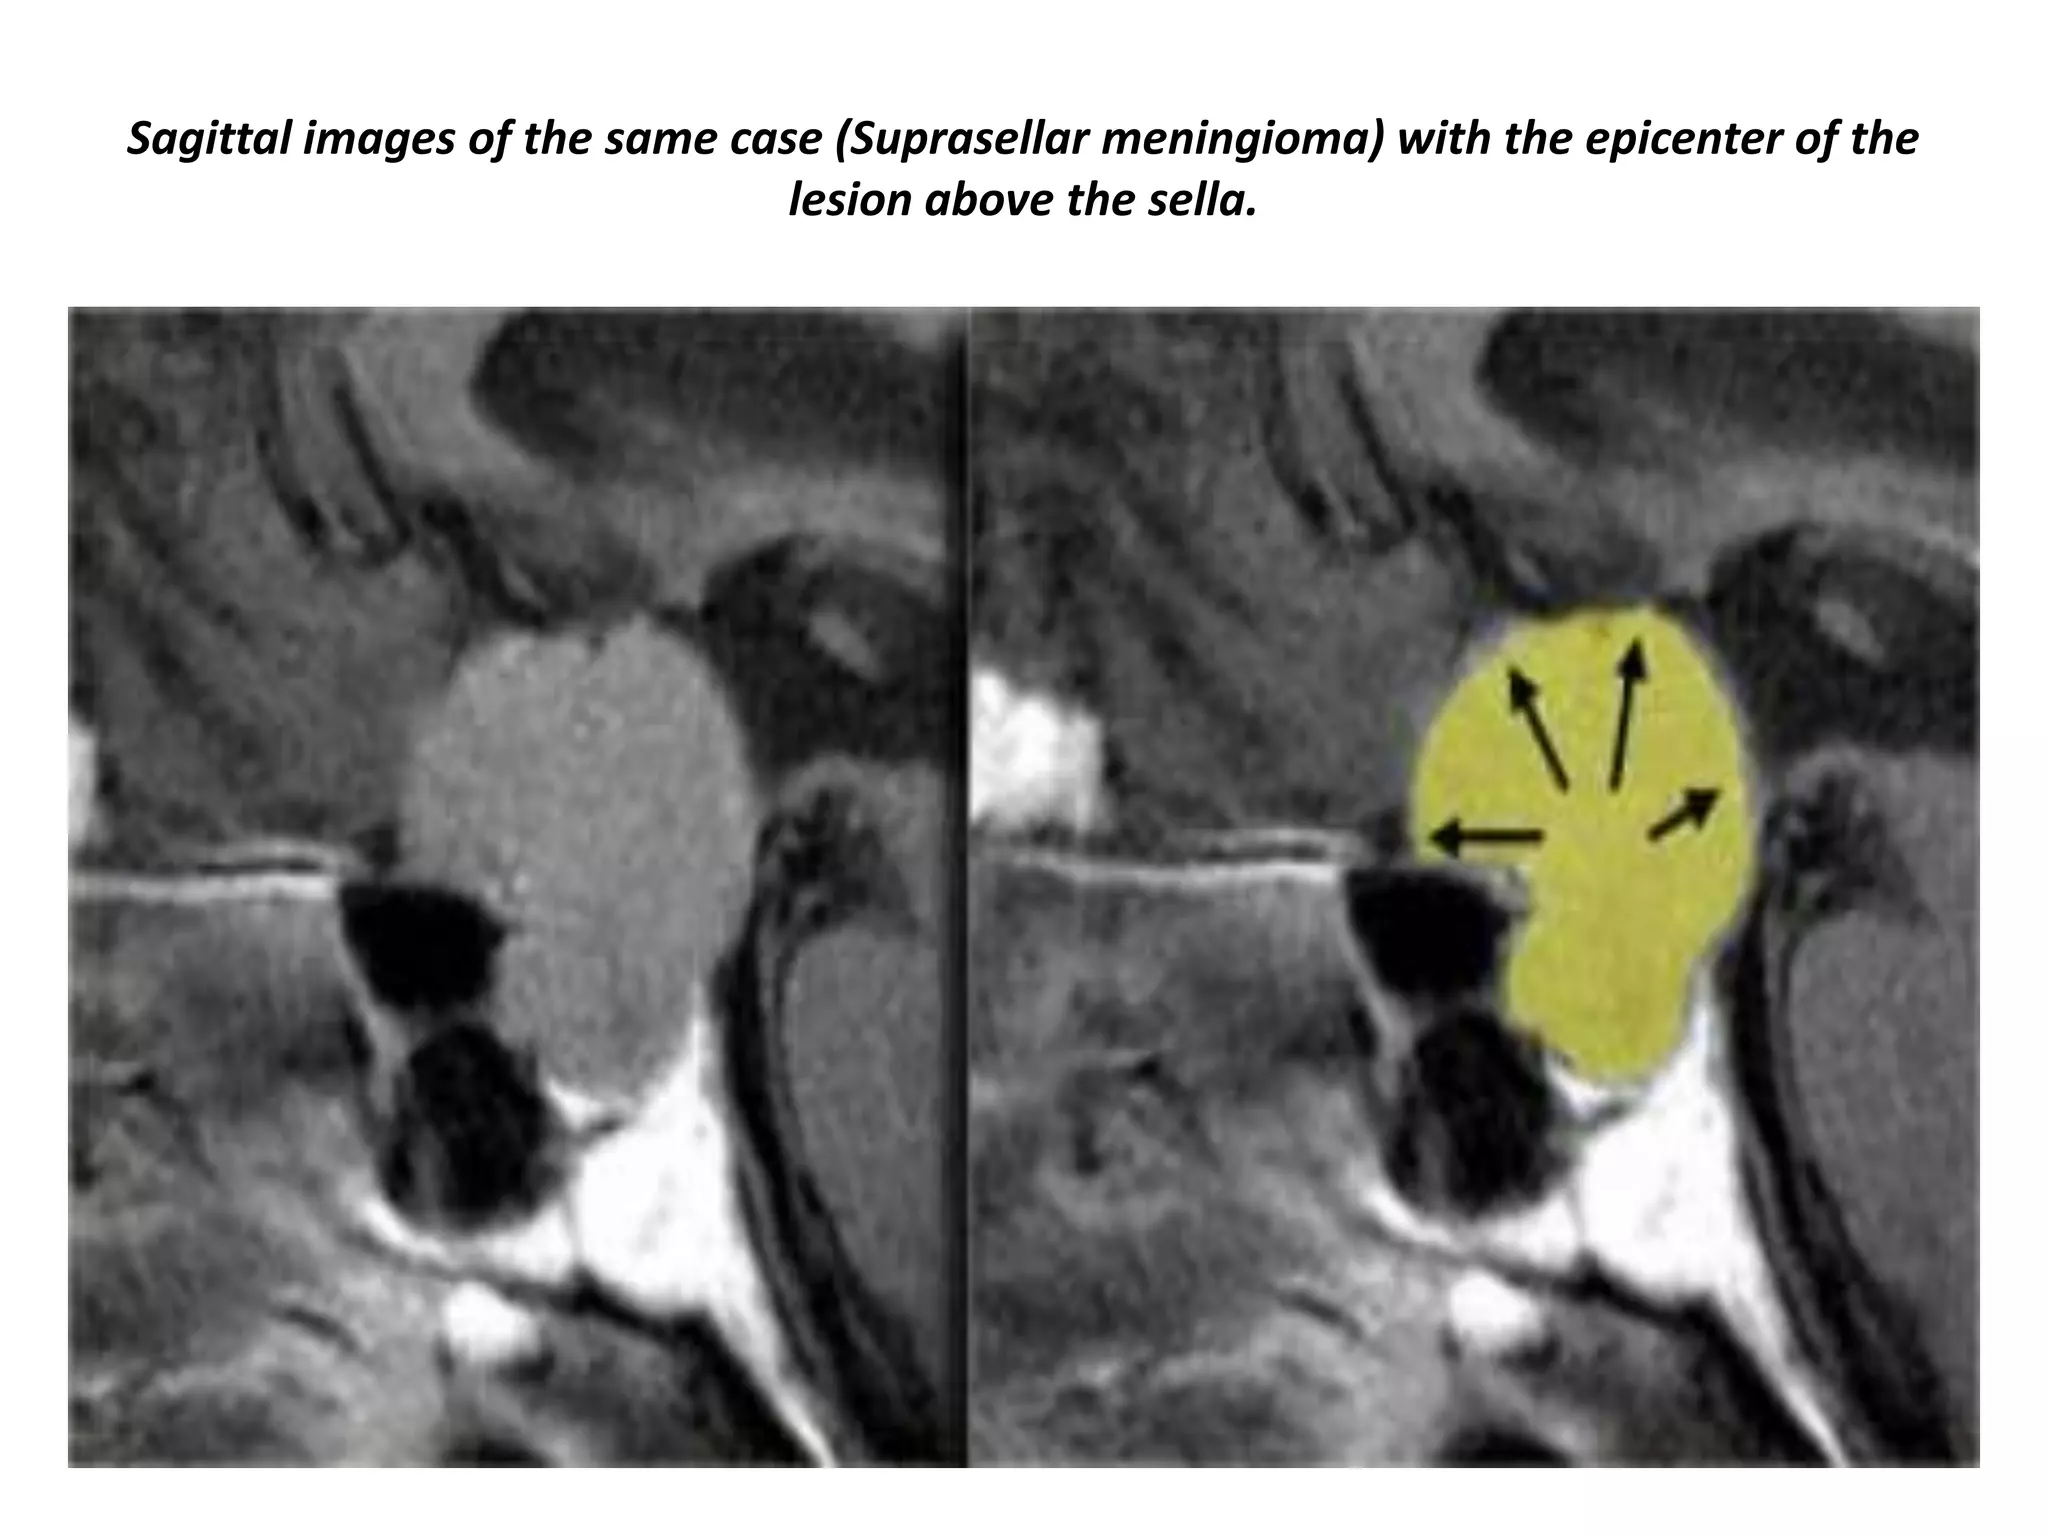

Supra-sellar meningioma with the epicenter of the lesion above the sella.

Sagittal images of the same case (Suprasellar meningioma) with the epicenter of the

lesion above the sella.